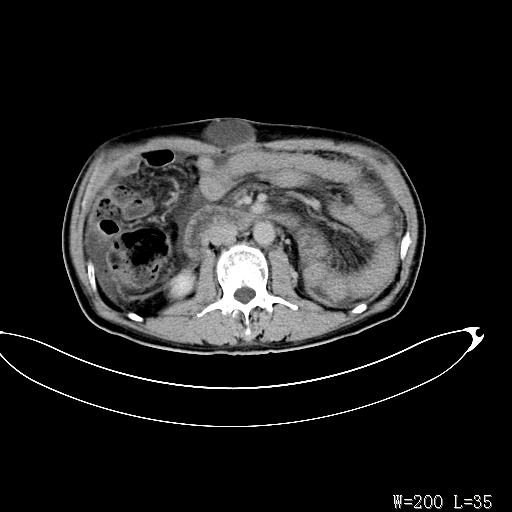

男,52岁,门脉高压断流术后1年,发现腹部肿物2月。

1)前腹壁中线区(脐上方)囊性占位性病变,考虑淋巴囊肿。2)腹水。